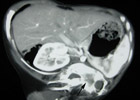

Bé được nhập viện và chụp tiếp CT scan bụng, kết quả có một khối u kích thước 14x13x12 cm gồm mô đặc, mô mỡ, mô xương kèm với hộp sọ, cột sống và xương sườn chiếm gần hết hạ sườn bên trái của bé. Dựa vào kết quả chẩn đoán hình ảnh và khám lâm sàng, các bác sĩ kết luận đây là trường hợp thai trong thai hiếm gặp.

ThS.BS Vũ Trường Nhân, phẫu thuật viên chính trong êkíp mổ, cho biết tình trạng “thai trong thai” là khi em bé mới sinh đã có một bào thai khác hoàn chỉnh nằm trong người. Đây thực chất là những cặp song sinh cùng trứng nhưng vì một nguyên nhân nào đó mà trong quá trình phát triển của phôi thai xảy ra tình trạng phôi này trùm lên phôi kia khiến phôi nằm trong phôi. Do vậy, khi sinh ra em bé đã có sẵn một bào thai nằm trong bụng. Y khoa gọi là hiện tượng song sinh phát triển không hoàn chỉnh, rất hiếm với tỉ lệ gặp là một trên nửa triệu ca.

Để đủ điều kiện gọi là thai trong thai thì bào thai được lấy ra trong bụng em bé phải có những bộ phận tay, chân, bộ phận sinh dục... và nhất thiết phải có cột sống. Các trường hợp khác cũng giống thai trong thai nhưng không có cột sống thì không gọi là thai trong thai mà chỉ là bướu quái dạng thai (tỉ lệ gặp nhiều hơn).